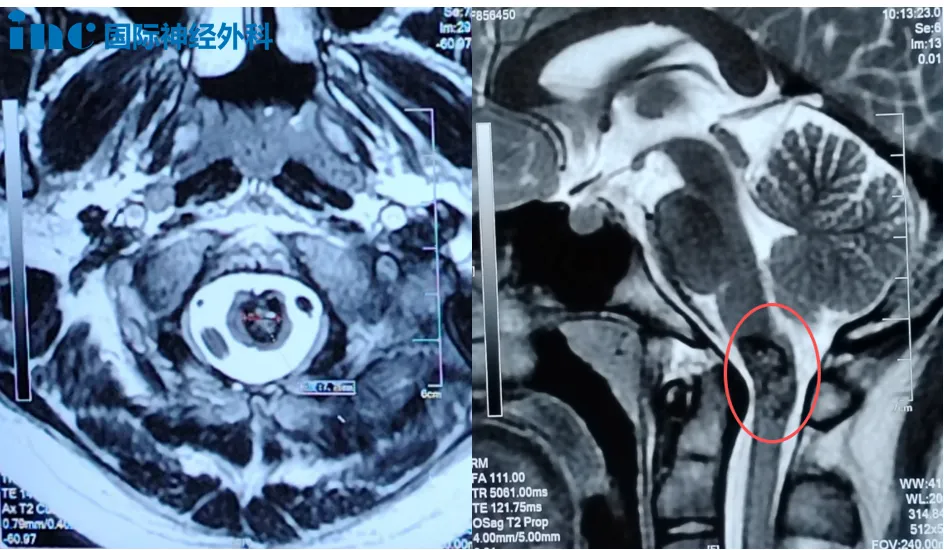

14岁男孩小宇,今年8月突然开始头痛、呕吐,手脚也阵阵发麻。头颅核磁检查提示,延髓异常信号,考虑海绵状血管瘤。这个听起来有些陌生的病变,就长在生命中枢所在的延髓与颈髓交界的要害位置。住院治疗十天后,小宇的症状好转。到了9月,所有不适都消失了,可复查的核磁仍提示:延颈交界处异常信号,直径约8mm。症状消失了,可病灶没有消失。